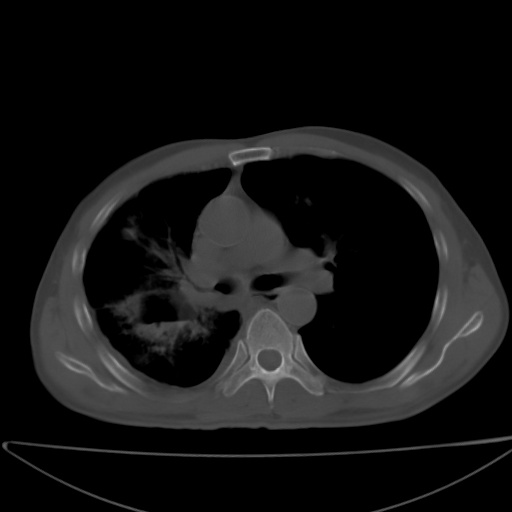

以下是引用jsgdoctor在2008-11-6 22:12:00的发言:[br]右主支气管壁明显增厚,管腔狭窄.考虑为右侧中央型肺癌伴阻塞性炎症\\肺脓肿.

以下是引用zjzjr在2008-11-6 20:25:00的发言:[br]中心型肺ca,合并阻塞性肺炎

以下是引用zsl6918在2008-11-6 19:43:00的发言:[br]右侧中心性肺癌(鳞癌)